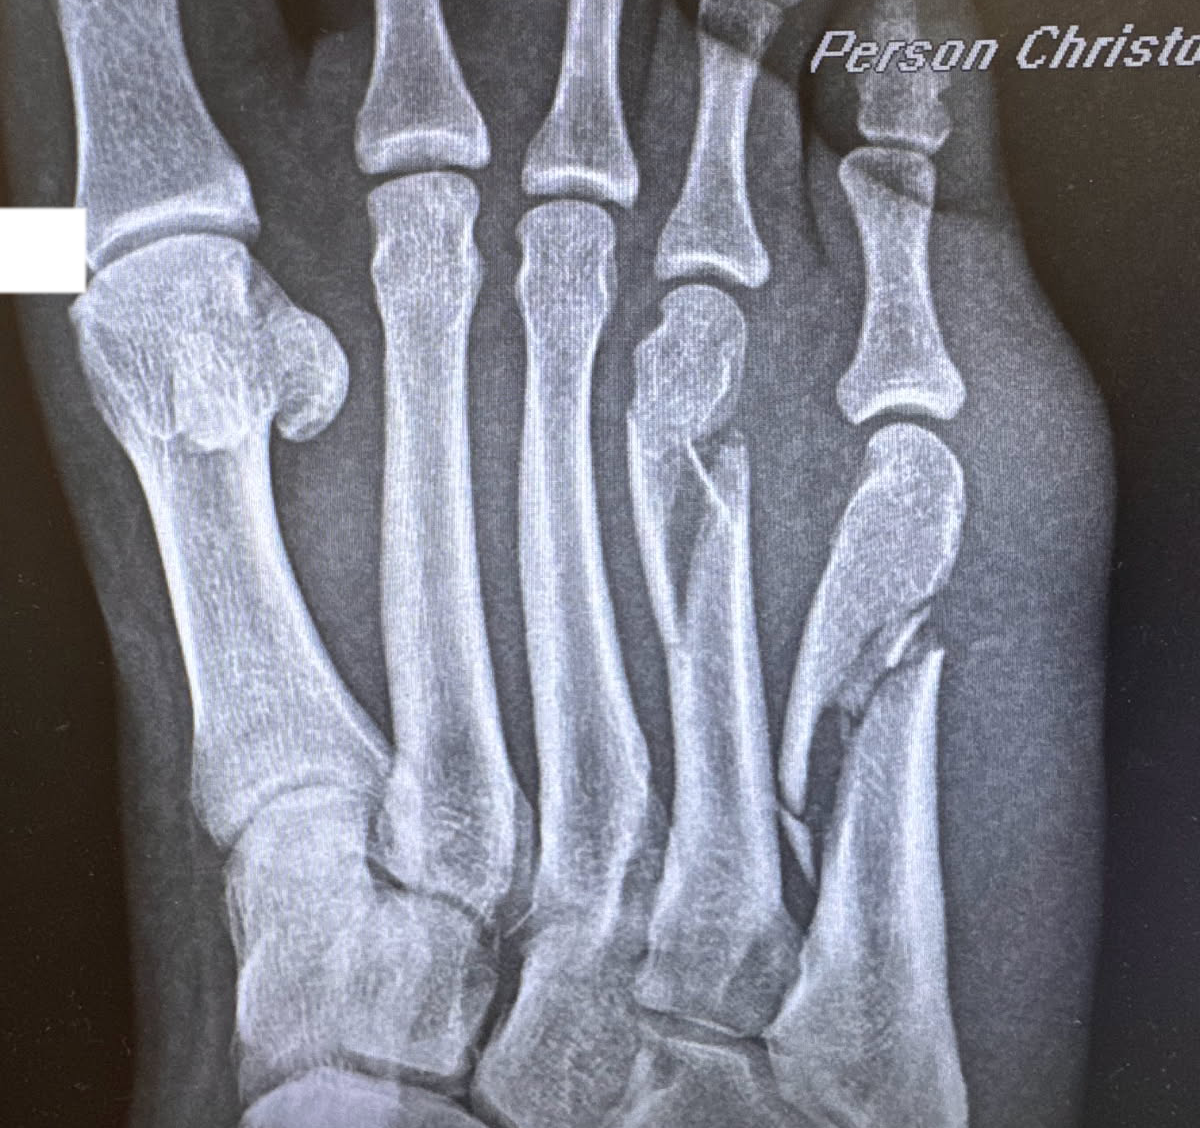

My foot is currently what the medical profession would call “busted.” This happened due to the structural collapse of a step, and the result was my 4th and 5th metatarsal being broken into two and “multiple” pieces respectively. Like Bart Simpson in the Rear Window parody episode “Bart of Darkness,” I am now forced to spend the remainder of my summer recuperating indoors while friends have fun. But there is one piece of gear that has made my life a little bit easier: the iWalkFree, a mobility aid that does not oversell itself and has helped me get back a tiny bit of mobility.

This time around, I took a spill in my backyard and immediately went to the hospital. For the second time in my life, I have a plate in my lower body, but at least I caught it early. Suddenly being on crutches is not a fun experience, but for me will be transitory. Lower leg breaks are a reminder that every non-disabled person is likely to gain a disability on a long enough timeline, some sooner than others, and what the limitations of the place you live in are (the MTA, for example, is so bad at this they got sued for it). It also requires relearning big parts of your life, and for me the hardest part was not going out and socializing but being able to go to the deli for a soda and putter around my house to do basic tasks. Grabbing several small tools scattered from around my house is like 50 percent of my day when I’m in project mode, and having an impediment slowed me to a snail’s pace.